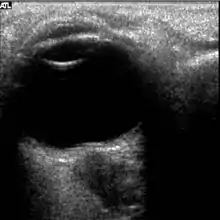

The astronauts affected by long term visual changes and prolonged intracranial hypertension have all been male, and SOS may explain this because in men, the sternocleidomastoid muscle is typically thicker than in women and may contribute to more compression. The reason that SOS does not occur in all individuals may be related to anatomic variations in the internal jugular vein. Ultrasound study has shown that in some individuals, the internal jugular vein is located in a more lateral position to Zone I compression, and therefore not as much compression will occur, allowing continued blood flow.

Intracranial pressure (ICP) needs to be directly measured before and after long duration flights to determine if microgravity causes the increased ICP. On the ground, lumbar puncture is the standard method of measuring cerebral spinal fluid pressure and ICP,[6][44] but this carries additional risk in-flight.[4] NASA is determining how to correlate ground-based MRI with inflight ultrasound[4] and other methods of measuring ICP in space is currently being investigated.[44]